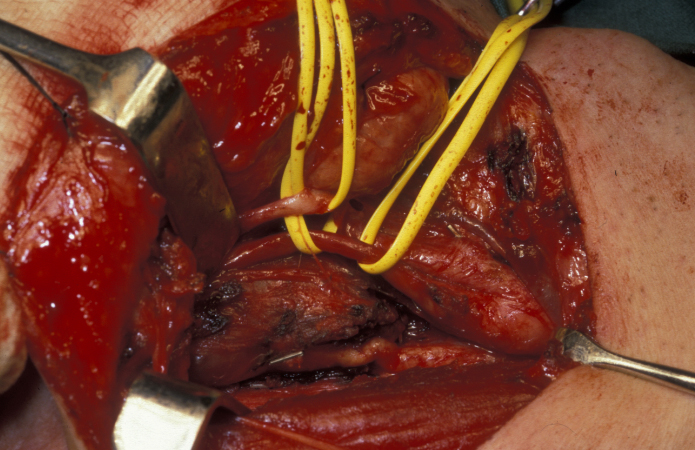

The majority of these neurogenic tumours (neurofibroma, Schwannoma) are slow-growing benign tumours. Approximately 25 to 40 % of these are found in the head and neck region. If possible / on balance, these tumours should be surgically removed: there is a small but significant risk of benign Schwannomas for malignant transformation (see Figure 3 and Figure 4).

Figure 3: Sympathetic chain schwannoma, these tumours can be very difficult to safely access and remove but this is possible without causing great damage.

Figure 4: Vagal schwannoma peeled out of the nerve sheath and preserving the structure of this important nerve. Note the resemblance to a new potato!